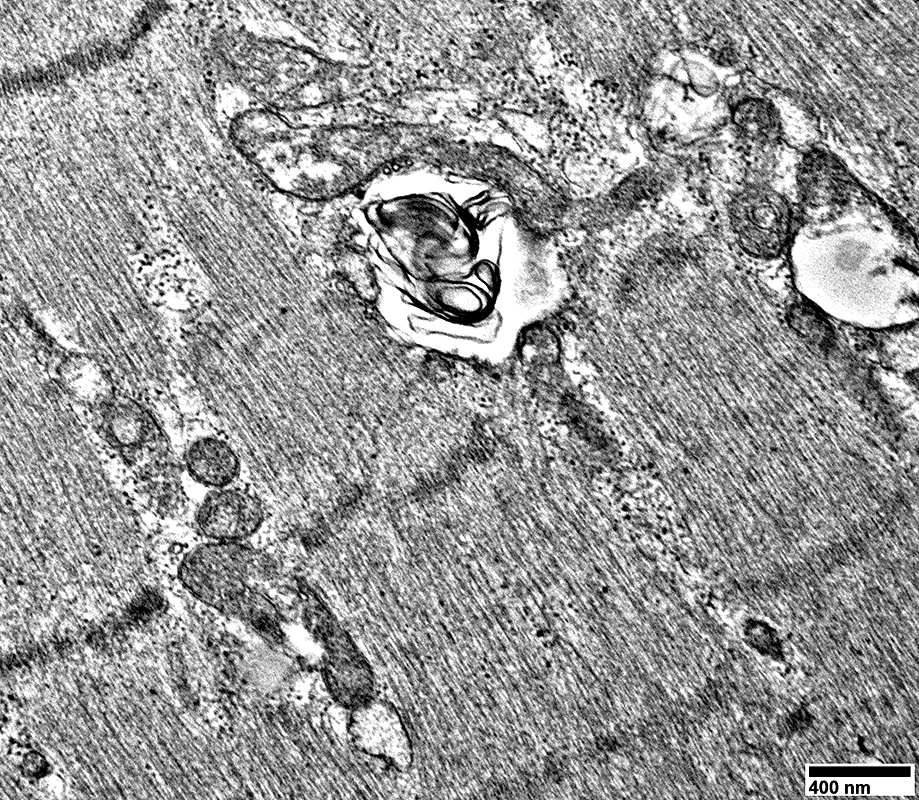

Large cells near vessels with

Mitochondrial proliferation & enlargement

Lipid droplets

From: R Schmidt

Large cells near vessels with cytoplasm nearly replaced by